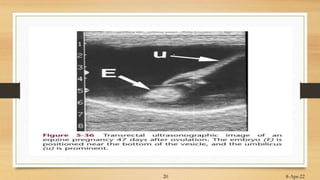

Ultrasonographic Method

Sex determination

• Genital Tubercle……at or afterward 55 day

• Precursor of penis (in male) or Clitoris (in female)

• Moves from position b/w hind legs to near tail……….Female

• Moves from position to near umbilicus……….Male